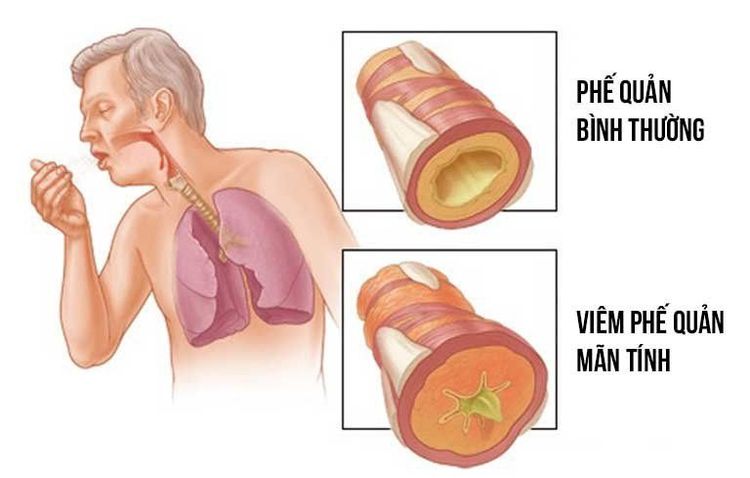

Đến nay, bệnh phổi tắc nghẽn mạn tính vẫn được đánh giá là bệnh khí phế thũng phổi và/ hoặc căn bệnh viêm phế quản tắc nghẽn gây nên.

Trong đó, viêm phế quản tắc nghẽn là tình trạng viêm và sưng mạn tính làm cho bên trong các ống thở (đường thở) nhỏ hơn bình thường. Sự thu hẹp này cản trở việc không khí thoát ra khỏi phổi tốt và dễ dàng.

Khí phế thũng hay còn được gọi là giãn phế nang, đặc trưng cho sự căng giãn thường xuyên, gây phá hủy không hồi phục tại thành của những khoang chứa khí bên dưới tiểu phế quản tận.